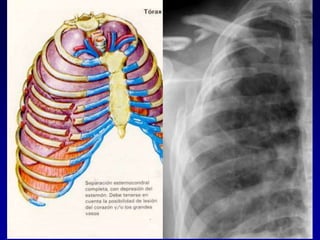

Causas Potenciales que Afectan

Tórax y la Respiración

Hemoneumotórax Neumotórax a

tensión

Contusión

Pulmonar

Tórax Inestable

Neumotórax abierto

 Trauma alta energía

 Fracturas de 3 o mas costillas en 2 o mas

sitios

 Contusión -Hemoneumotorax

 Falla ventilatoria

TRAUMA PEDIATRICO

TORAX INESTABLE